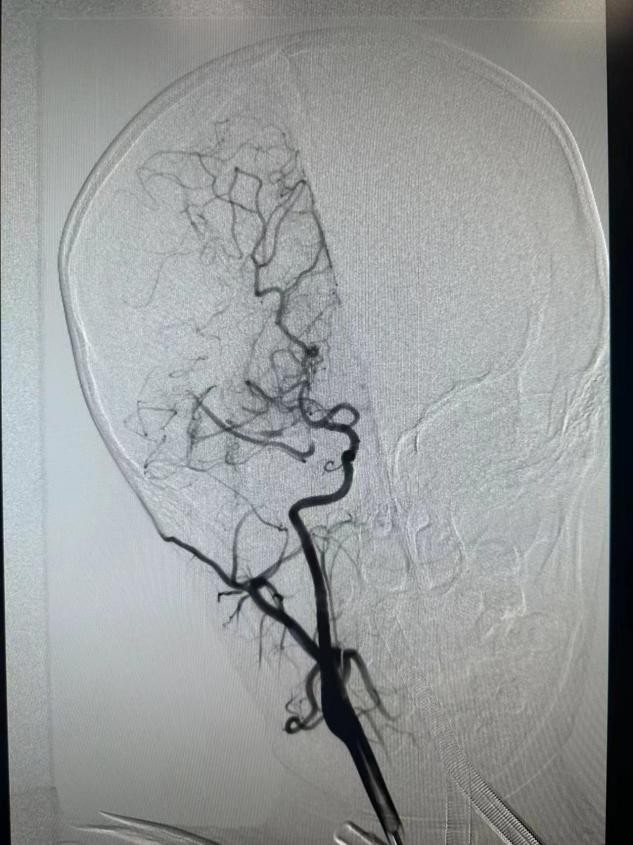

在麻醉科、小儿重症医学科等专业人员床旁监护下,介入团队成功在患儿脑组织窗内进行介入手术,在右股动脉取0.27cm的微小通路,同时置入100cm的导管进行脑血管造影后,明确右侧大脑中动脉起始段闭塞,随后使用专用的脑血栓抽吸装置缓慢抽吸血栓,在经历了90分钟的手术后,成功取出患儿“肇事血栓”,右侧大脑中动脉前向血流恢复,为患儿疏通了“生命河流”。

造影明确责任血管